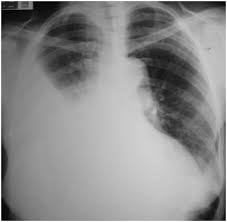

HEMOTORAX

El 'hemotórax es la presencia de sangre en la cavidad pleural. Generalmente está causado por lesiones torácicas, (arterias)pero puede haber otras causas, tales comocáncer pulmonar o pleural, o incluso cirugías torácicas o del corazón.

Los síntomas del hemotórax son: dificultad para respirar, dolor torácico, ansiedad o inquietud, y frecuencia cardíaca acelerada. El médico puede confirmar su diagnóstico con un examen físico que puede revelar una disminución de ruidos respiratorios, la aparición de matidez a la percusión, o por medio de una radiografía de tórax